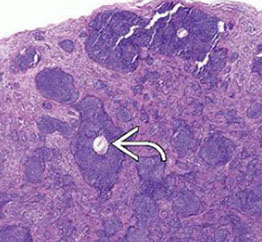

Spiradenoma

Usually presents as solitary, violaceous, gray-blue nodule that tends to arise on the ventral aspect of the head, neck, trunk, and sometimes extremities

- usually young adults (15-35 yo), can be painful

May be found in Brooke-Spiegler syndrome (cylindromas, spiradenomas, trichoepitheliomas)

Closely related to cylindroma (may occur as a hybrid tumor), those these are usually sporadic whereas cylindromas are multiple and inherited

- spiradenomas may present as a tender nodule

Micro: Large ball of dark blue cells (cannonballs) that are not attached to the epidermis tc interspersed black lymphs and paler cells in the middle of the ball c dark red droplets of hyaline

DDx: considered sometimes to be on a spectrum with cylindroma